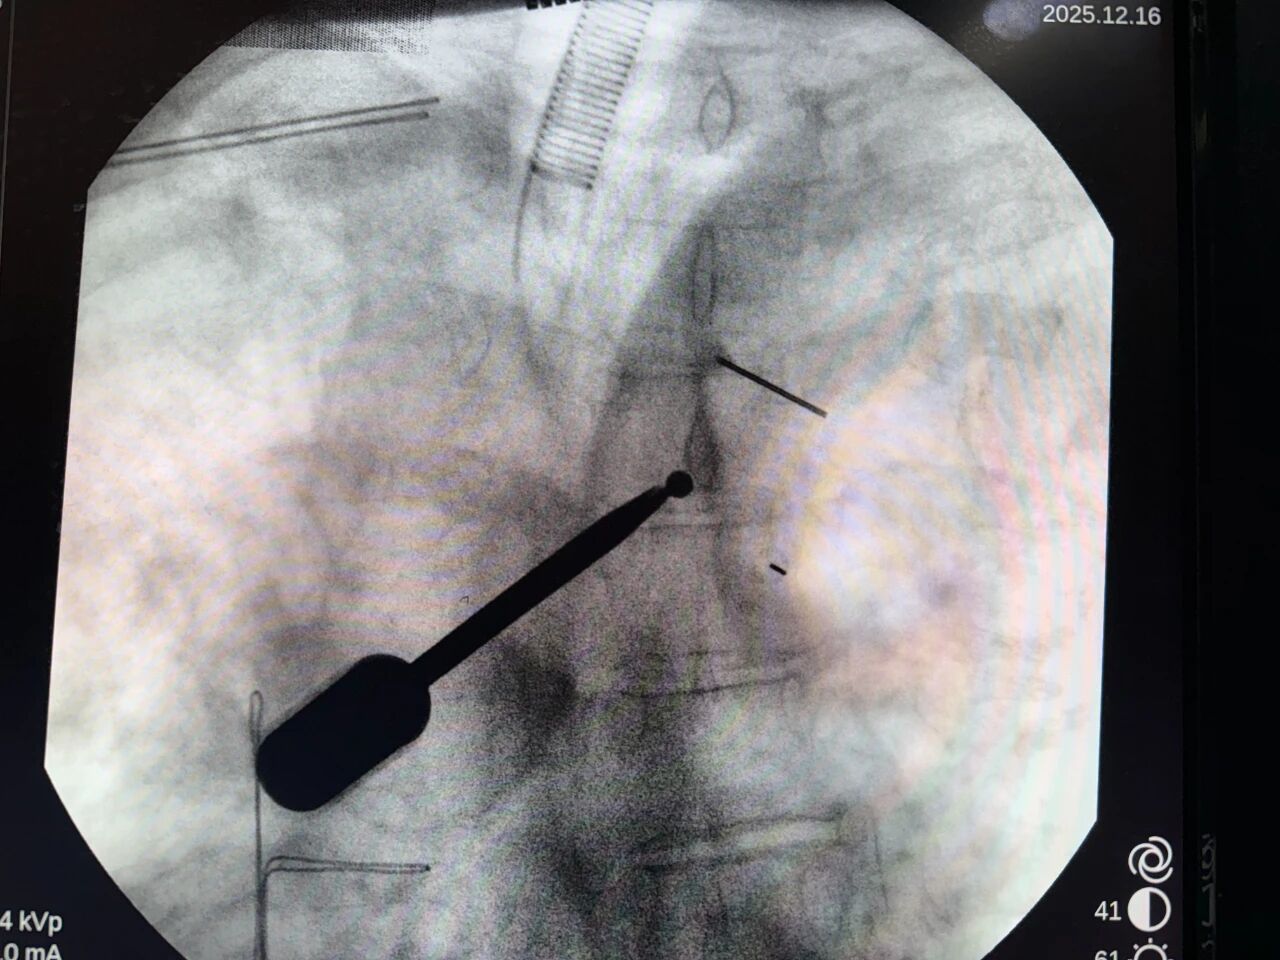

结合患者影像资料及整体身体状况,吕海提出采用 UBE 微创技术实施椎管内肿瘤切除手术。「胸段脊髓位置深、周围神经血管密集,既要彻底切除肿瘤,又要最大限度保护脊髓功能,对手术精度要求极高。」吕海介绍,UBE 微创技术通过双通道设计,在高清内镜直视下完成操作,切口仅约 1 厘米,创伤小、出血少、恢复快,尤其适合高龄及合并多种基础疾病的患者。

在我院手术室及麻醉、护理等多学科团队的密切配合下,吕海与李毛召同台协作,历时 3 小时,顺利完成手术。

术中,在高清内镜引导下,肿瘤被精准剥离并完整切除,脊髓及周围神经结构得到充分保护。